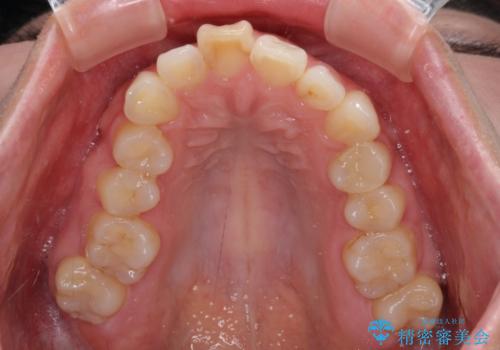

- 上顎前歯の突出感と、前歯のクロスバイトを気にして来院された患者様です。

前歯の叢生と口元の閉じにくさを気にして来院された患者様です。

奥歯の咬み合わせを見ると、上顎が下顎に対して相対的に前方にありました。

口元の閉じにくさを改善するためには、上顎臼歯を後方に移動させた咬み合わせにする必要があります。

インビザライン単体で改善することも可能ですが、達成する可能性が高くないため、カリエールディスタライザーという補助装置を併用して、より確実性を上げることとしました。

奥歯の咬み合わせを改善しながら、並行してインビザラインで歯列を整えることとしました。

カリエール・ディスタライザーを用いたことで上顎前歯の突出感はスムーズに解消され、歯列不正は1年半ほどでほぼ改善することができました。

しかし、その後インビザライン特有の奥歯がうまく噛めないという問題が長引き、改善に1年近い期間を要することとなりました。